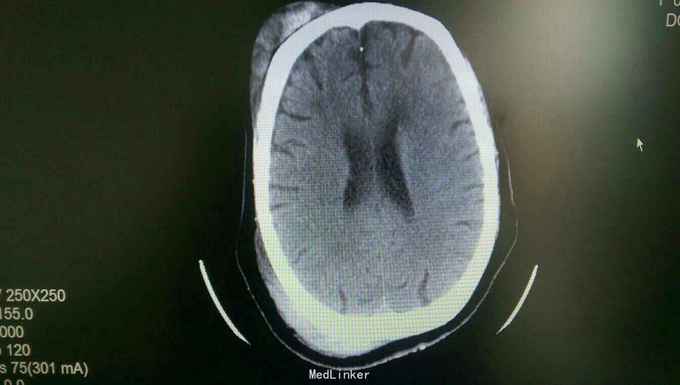

查体:体温36.2,脉搏104次/分,呼吸22次/分,血压80/40mmhg。患者嗜睡,急病容,痛苦貌。右额顶部巨大头皮血中,伴头皮挫裂伤,有出血。瞳孔等大,光反存在。耳鼻,口腔无出血。气管居中。右侧胸廓畸形,胸廓挤压痛明显。右侧呼吸音低,可闻及湿啰音。心率104次/分,律齐。未闻及病理性杂音。腹部平软,全腹无压痛,肠鸣音存在,腹腔穿刺未抽出血性液体。肾区叩击痛阴性。胸腰椎有明显压痛。四肢无畸形,活动可。神经系统无异常。 辅查:头颅ct示:外伤性蛛血,右额顶部巨大血肿。胸部ct示:右第3--12肋骨折(8-10骨折端明显错位,并见骨折端刺入右下肺组织),左8-9肋骨折。伴右肺上下叶及左上叶肺挫伤。双侧液气胸。右胸壁皮下气肿。胸椎9-11棘突骨折,胸11椎体骨折可能,腰1-2右横突骨折。